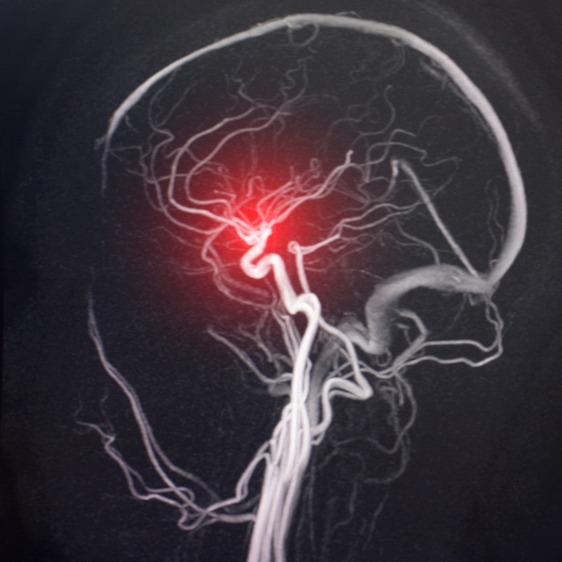

• imaging cerebrale: l’ausilio di test di imaging come la tomografia computerizzata (TC) o la risonanza magnetica (RM) può permettere di identificare eventuali lesioni o ostruzioni nell’arteria cerebrale;